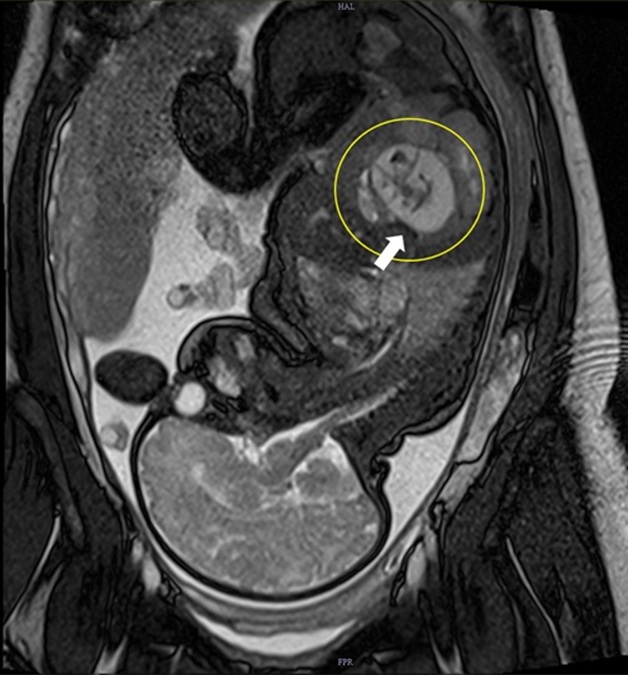

The condition was first diagnosed at the antenatal scanning done by Dr Vivek Krishnan, Additional Professor, Dr. Dhanya Keezhatoor and Dr. Sruthi Soman, Assistant Professors from the department of fetal care. Advanced prenatal imaging revealed an abnormal mass, prompting close monitoring and expert evaluation. Antenatal scans play a crucial role in identifying such complex conditions early, enabling timely intervention after birth.

After delivery, further imaging confirmed the presence of fetus in fetu—a non-viable twin entrapped inside the abdomen of the surviving infant. At just two months old, the baby girl underwent a complex open surgery at Amrita Hospital to remove the malformed fetus, which weighed 48.7 grams.